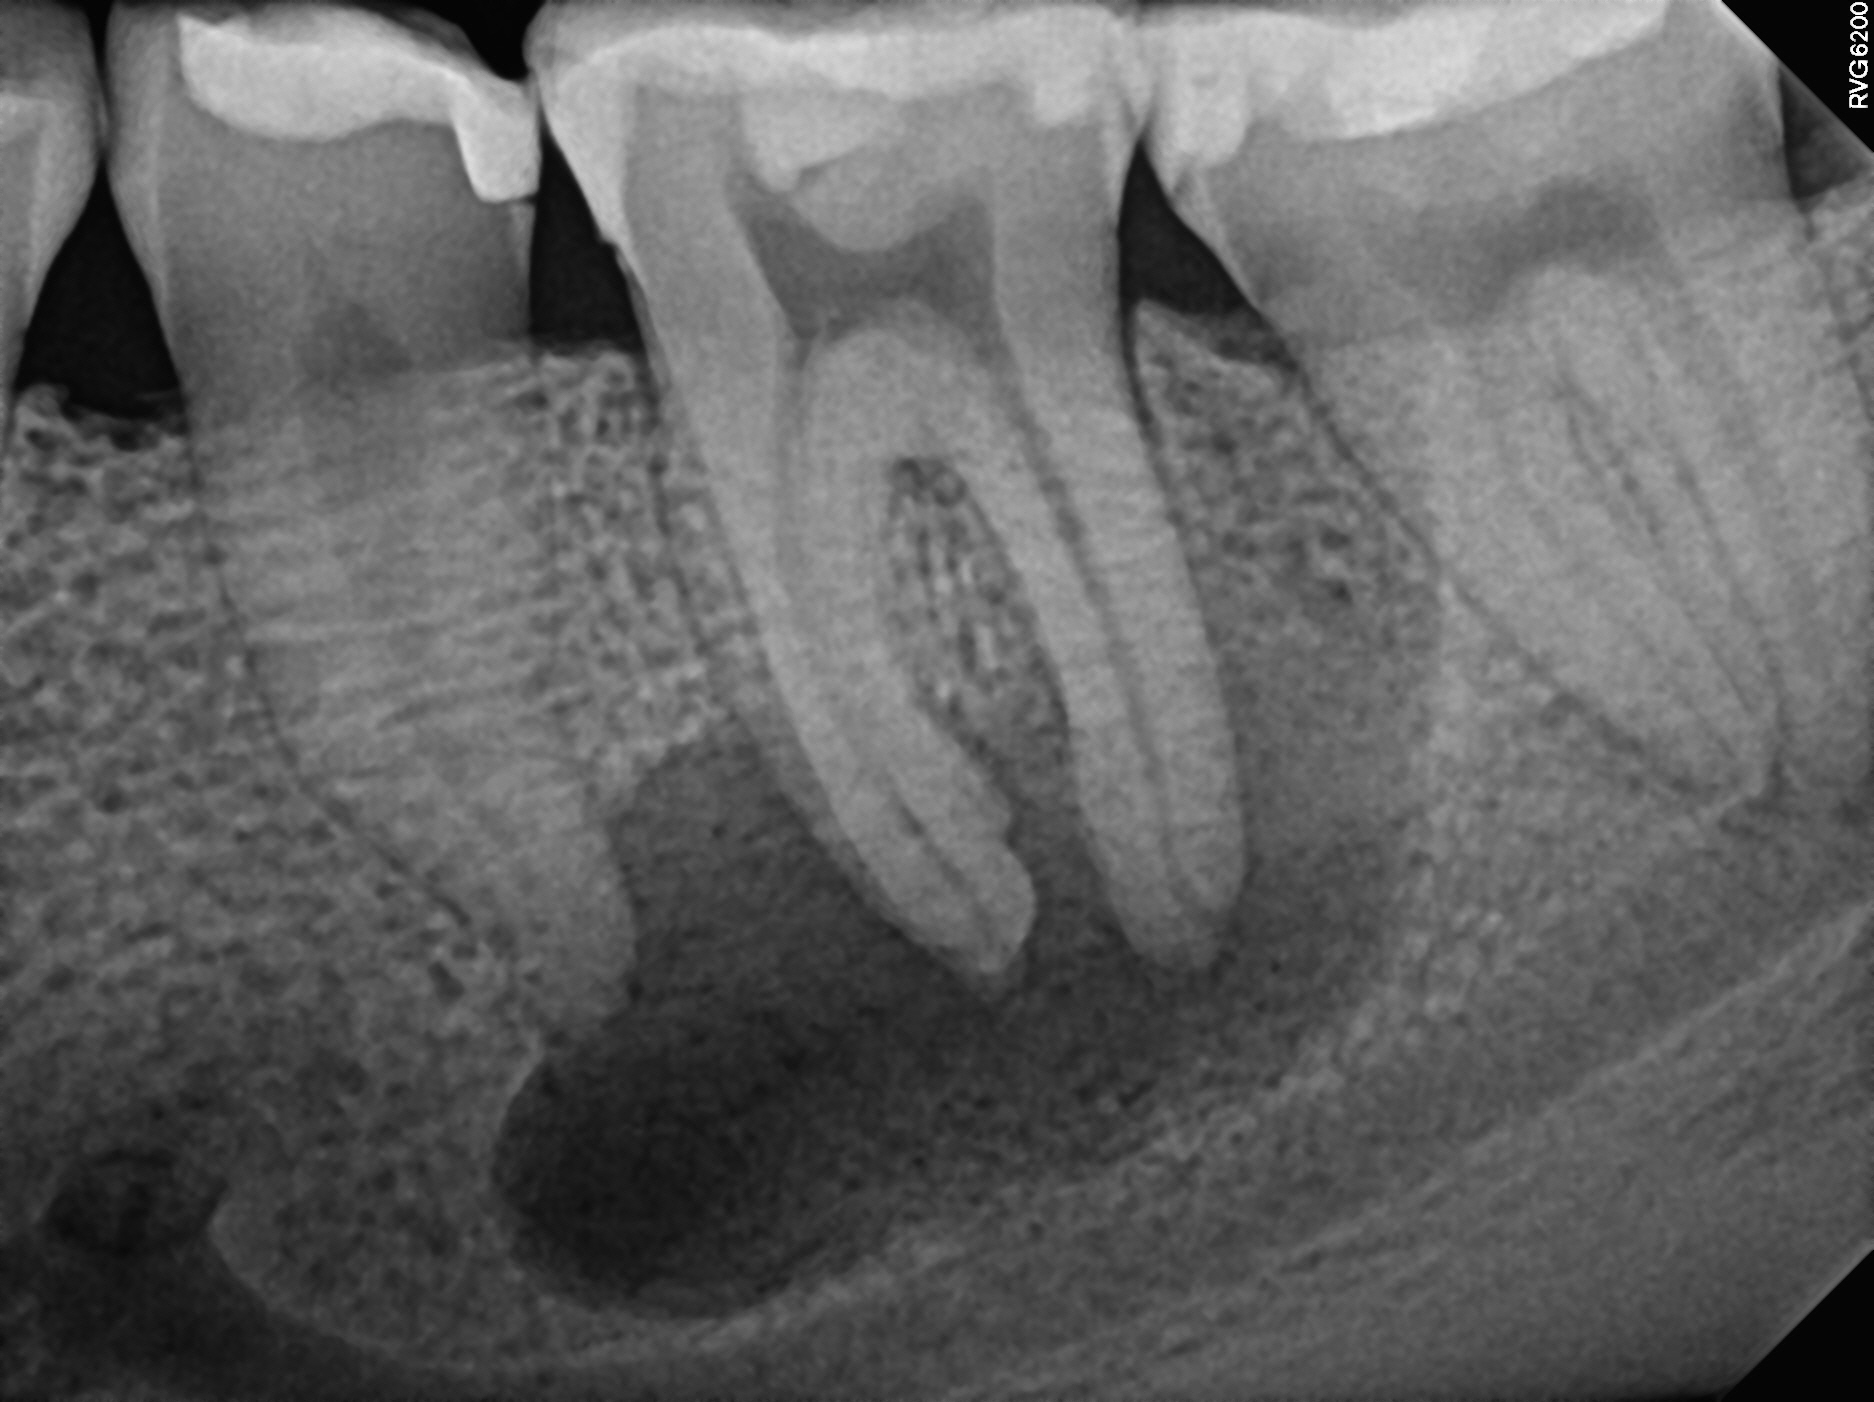

Case 10

This case also highlights curved roots. The first image is before treatment--notice the abscess in the bone (the dark shadows at the root tips). The second is during treatment and you can see the filling materials in the sharp curve of one of the roots. The third image is the immediate post-treatment image. The fourth image is one year later--notice the abscess (the dark shadows at the root tips) has healed. Unfortunately the tooth was never restored with a permanent filling or crown and the tooth had broken down further at this point and may need to be extracted despite the infection healing perfectly--it's critical to follow up with your general dentist for a final restoration!